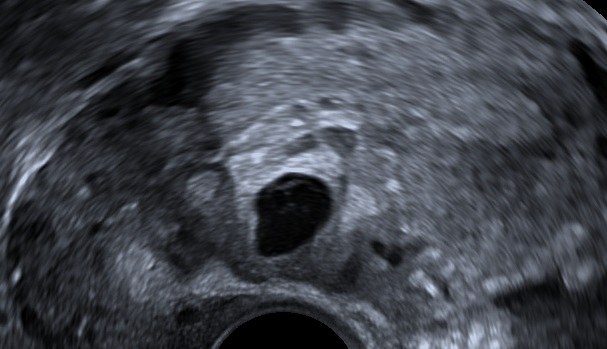

The following ultrasound criteria may be used for the diagnosis of caesarean scar ectopic pregnancy: Empty uterine cavity, gestational sac or solid mass of trophoblast located anteriorly at the level of the internal os embedded at the site of the previous lower uterine segment caesarean section scar, thin or absent layer of myometrium between the gestational sac and the bladder, evidence of prominent trophoblastic / placental circulation on Doppler examination and empty endocervical canal (Elson CJ et al., 2016).